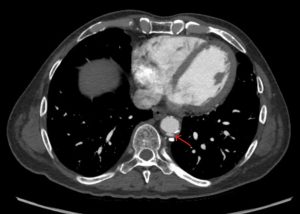

Exercise Testing for Pulmonary Embolism

Symptomatic patients who present with pulmonary embolism will present with shortness of breath and chest pain. Acutely, their functional capabilities are limited. While most patients post pulmonary embolism recover, many linger. Some patients who have suffered a pulmonary embolism will report limitations many months after the event. This is most pronounced after submassive- and massive…